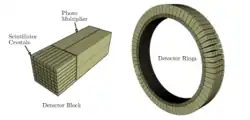

Der Detektor eines heute erhältlichen PET-Scanners besteht aus mehreren Detektorringen, die jeweils aus 30–40 Detektormodulen aufgebaut sind. Ein Detektormodul besteht aus 4–8 Detektorblöcken. Ein Detektorblock besteht aus mehreren Einzelkristallen (z. B. in der Anordnung 4×4, 4×5 oder 6×6). Die Abmessungen der Kristalle bewegen sich im Bereich von 6 bis 8 mm in transaxialer Richtung. In radialer Richtung – also in Einfallsrichtung der Photonen – beträgt die Kristalldicke meist zwischen 20 und 30 mm. In der Summe ergibt dies ca. 10.000 ringförmig angeordnete Detektorkristalle (Szintillationszähler), die bei analogen Systemen mit ca. 1000 Photomultipliern gekoppelt sind. Das Konstruktionsprinzip, bei dem ein Block von Photomultipliern auf ein Array von Szintillationskristallen „blickt“, wurde im Jahr 1986 eingeführt und hat sich seither bewährt.[4]

Der axiale Sichtbereich der Detektoren – auch Field of View (FOV) genannt – liegt meist im Bereich von ca. 15 bis 30 cm; bei hochpreisigen Systemen, die seit Ende der 2010er Jahre angeboten werden, ist er größer. Der Durchmesser des Detektor-Ringes liegt je nach Gerät zwischen ca. 50 und ca. 85 cm.

Die Szintillationskristalle werden entweder eingesägt, oder mehrere Kristalle werden miteinander verklebt. An den Kristallgrenzen kommt es zur Reflexion der Photonen, die so in Richtung der Detektoren gelenkt werden. Dies ermöglicht eine genauere Lokalisation als in einem homogenen, einzelnen Kristallblock. Mehrere Photomultiplier „blickten“ zusammen auf eine Gruppe von Szintillationskristallen und waren entweder direkt oder über Lichtleiter mit dem Szintillationskristall verbunden. Die Lokalisation der Szintillationen erfolgt nach dem Prinzip der Anger-Kamera durch Wichtung der Helligkeit der in den Photomultipliern registrierten Szintillationen.